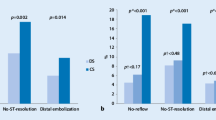

Thrombolysis in MI (TIMI) flow grade 3 was found in 96.7% and 63.3% of the patients of the PBSG and CDSG, respectively (P = 0.005). The results of the PBSG and CDSG are respectively shown as follows: 0% versus 30% no-reflow or slow flow (P = 0.002); 90% versus 66.7% ST-segment resolution ≥ 50% (P = 0.028); 35.6 ± 14.5 frames versus 49.18 ± 25.2 frames on corrected TIMI frame count (P = 0.014); and 60% versus 20% myocardial blush grade 3 (P = 0.001). At 1 month, the major cardiovascular adverse event (cardiovascular mortality) rate was 3.3% in both groups; at 1 year, the rate was 3.3% and 6.7% for the PBSG and CDSG, respectively (P = 1.00). In the CMR subset of cases, the presence of microvascular obstruction (MVO) was detected in 6.7% and 50% of the patients in the PBSG and CDSG, respectively (P = 0.023).

The proportion of patients with an immediate TIMI flow grade < 3 was lower in the PBSG than that in the CDSG after stent deployment (3.3% vs. 36.6%, respectively, P = 0.005) (Table 2). The no-reflow proportion of patients was lower in the PBSG than that in the CDSG (0% vs. 30%, respectively, P = 0.002). The corrected TIMI frame count was lower in the PBSG than that in the CDSG (35.6 ± 14.5 vs. 49.18 ± 25.2, respectively, P = 0.014), and more patients in the PBSG had ST-segment resolution ≥ 50% than that in the CDSG (90% vs. 66.7%, respectively, P = 0.028). The percentage of patients who achieved an MBG of 3 was higher in the PBSG than that in the CDSG (60% vs. 20%, P = 0.001).

Secondary outcome

There was no significant difference in the procedure time, radiation exposure time, or contrast volume between the two groups. The number of bleeding events and clinical end points were also not significantly different between the two groups (Table 2). The result of the subgroup analysis (Fig. 2) showed that male patients (RR = 1.46; 95% confidence interval [CI] = 1.09–1.94), non-thrombectomy (RR = 1.40; 95% CI = 1.05–1.86), high thrombus burden (RR = 1.52; 95% CI = 1.07–2.16), door-to-balloon time < 90 min (RR = 1.81; 95% CI = 1.24–2.64), and non-anterior wall infarction (RR = 2.53; 95% CI = 1.60–4.02) had a lower risk for no-reflow phenomenon, which favors PBSG (P for interaction = 0.07). According to the CMR subset, the PBSG can reduce the incidence of MVO and improve cardiac function (Table 3, Fig. 3).